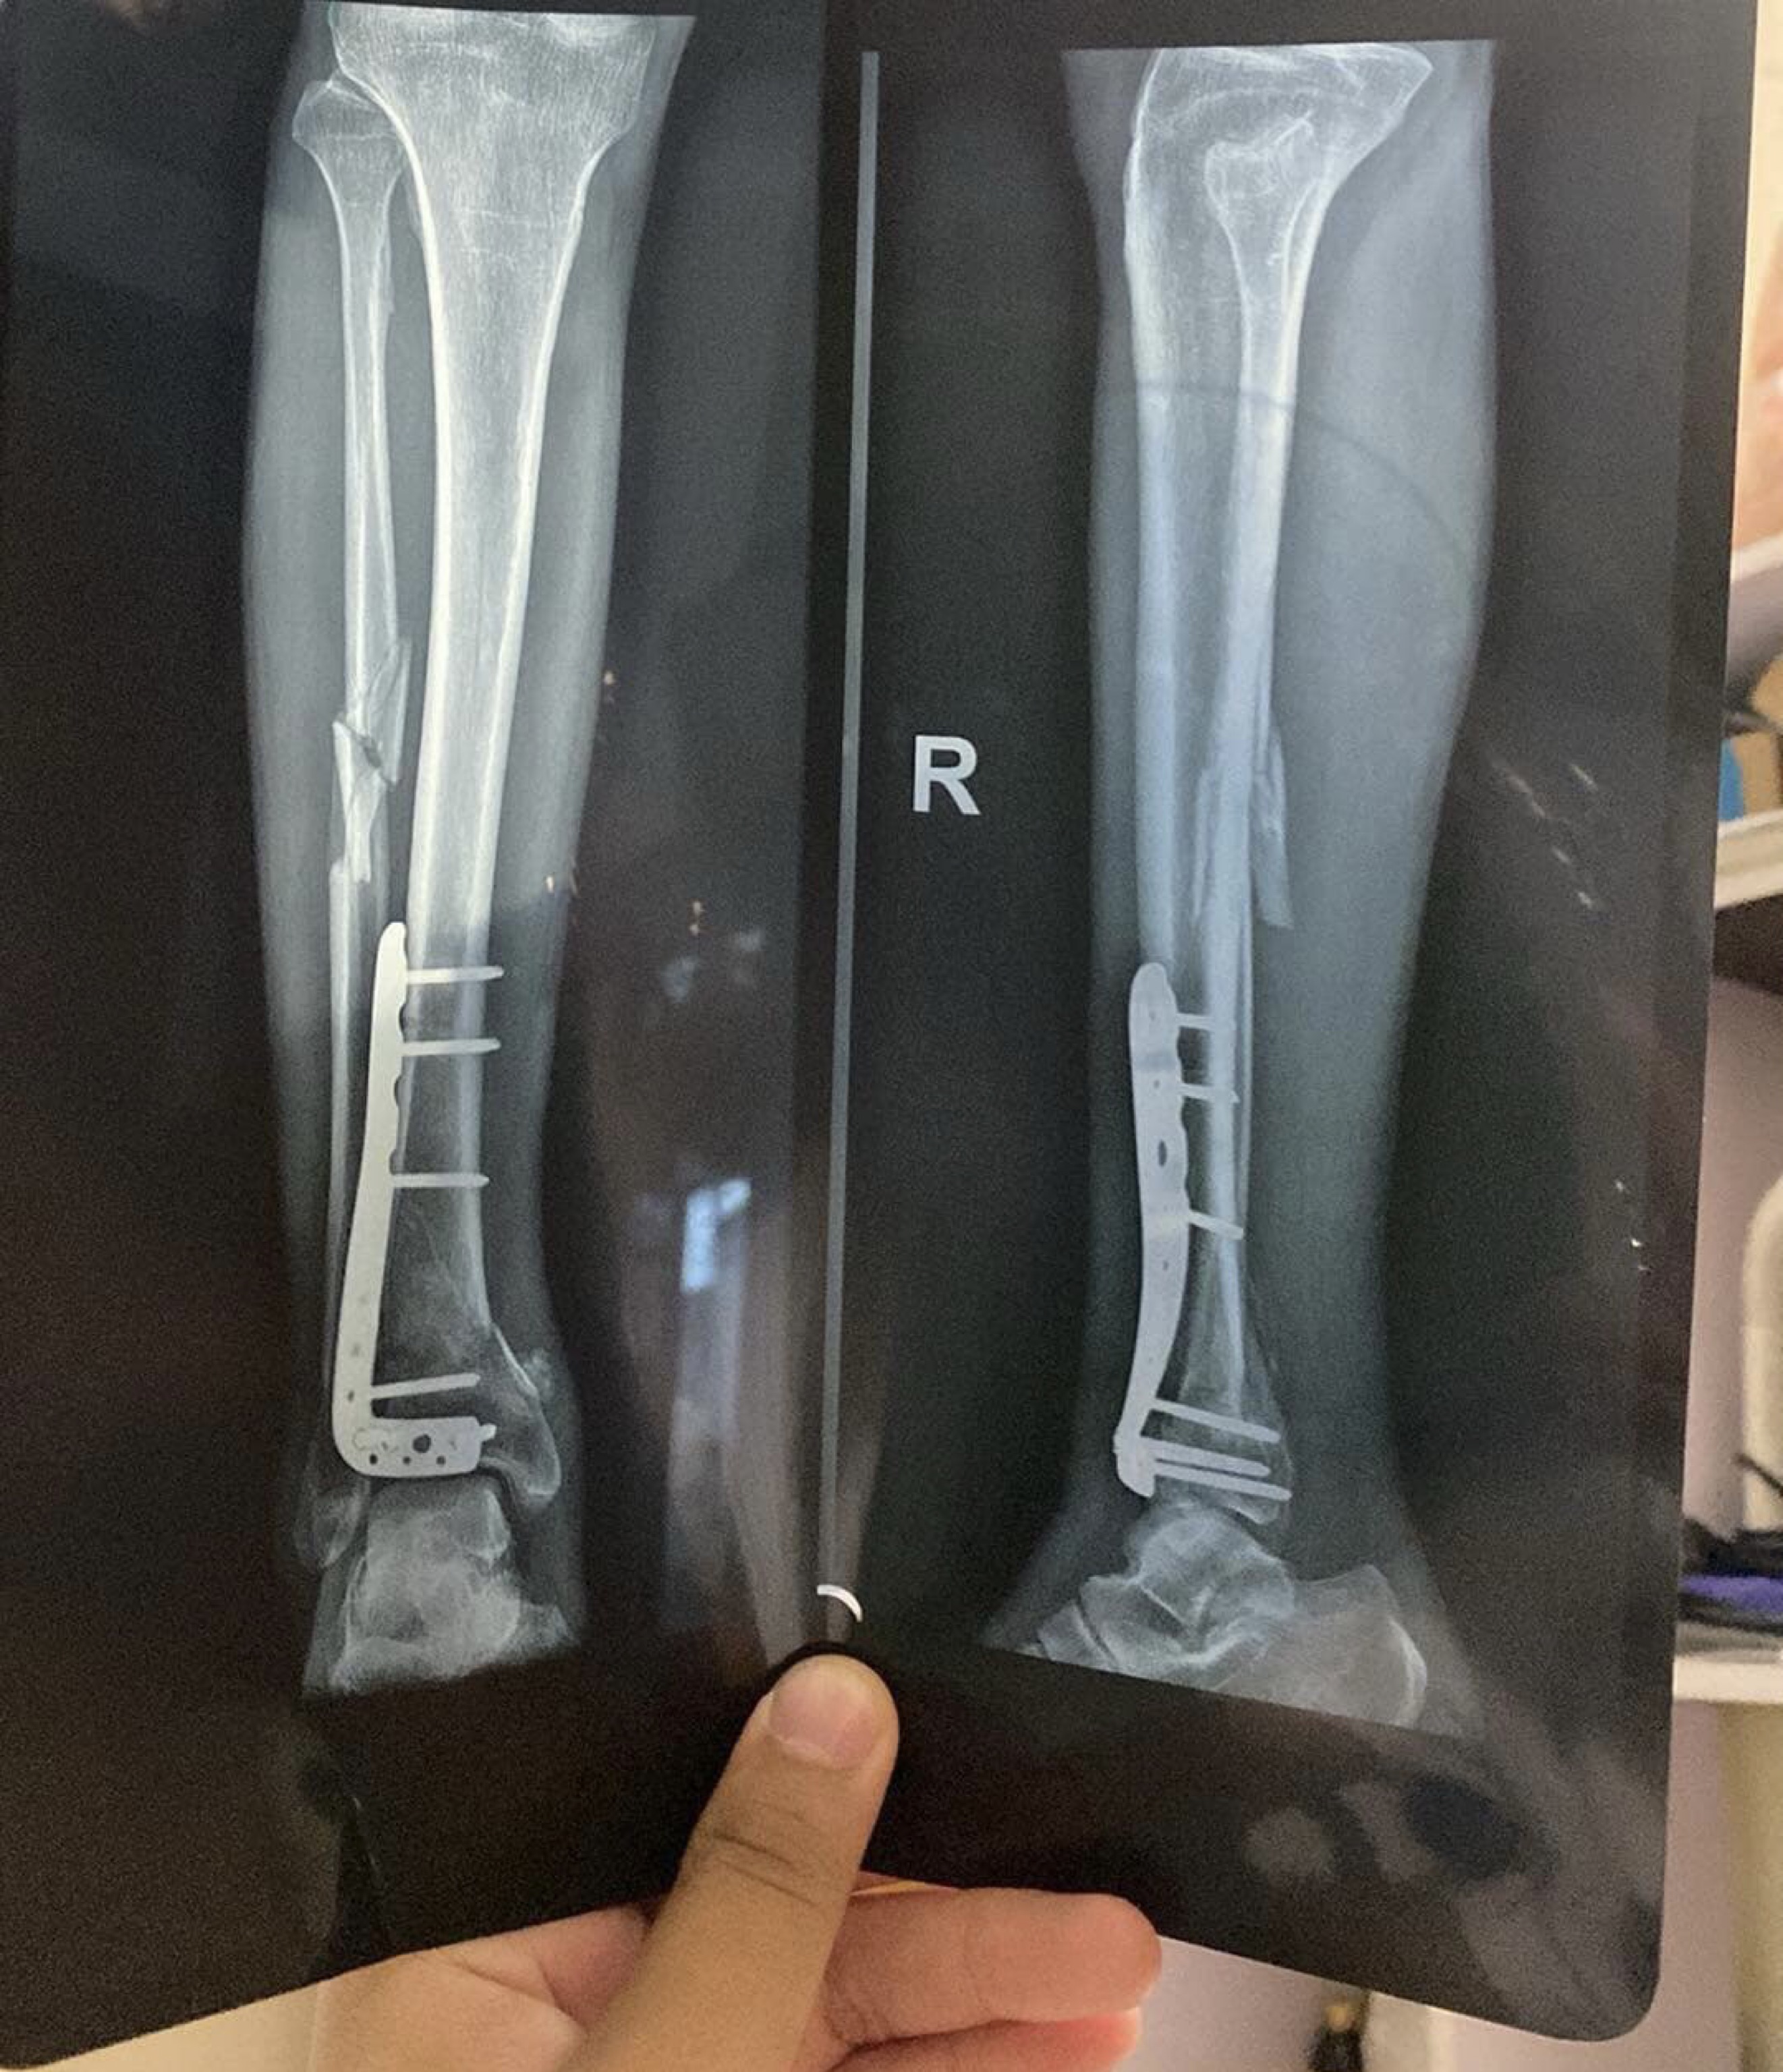

Bác sĩ ơi cho em hỏi bố em 54tuổi bị gãy xương cẳng chân phải phải mổ đóng đinh đến nay đã được 2 tháng nhưng chưa đặt chân xuống đi được và vẫn phải dùng lạng vậy bác sĩ cho e hỏi bao lâu bố em có thể tự đi được mà k cần lạng ạ